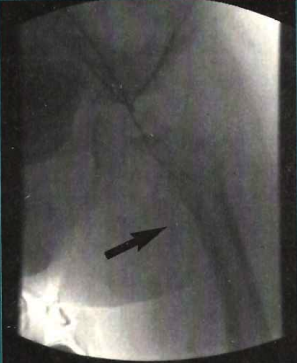

Case 1. A 2-year-old male patient with no history of systemic illness was taken to an area hospital by his parents due to vomiting and poor oral intake of over the previous 3 days. Upon arrival to the hospital, the patient was severely dehydrated and lethargic. Fluid resuscitation was started when he was found to be hypotensive. Laboratory reports demonstrated a glucose level of 1,200 mg/dl, large ketones, low CO2 at 5 mEq/L and a pH of 6.9. Fluids were adjusted, but the patient became obtunded and was intubated. Arterial and venous femoral catheters were inserted in the left side. Less than 12 hours later, the left leg became pulseless and pale, therefore, both catheters were removed and heparinization was initiated. Twelve hours later, cyanotic changes up to the mid-thigh were observed, without improvement of his pulse in the distal aspect of the extremity. During our evaluation approximately 26 hours later, the patient’s leg had obvious necrotic changes up to the femoral area, with cyanosis, ecchymoses and bullas. The leg also did not respond to pain stimulation and remained pulseless, even with Doppler evaluation. The patient was taken to the catheterization laboratory where arteriography via a contralateral femoral approach revealed total obstruction of the left iliofemoral arterial system.

Case 2. A 20-hour-old baby boy was born by cesarean-section at another facility after an uncomplicated first pregnancy. Upon birth, the baby was found to have a bulla in the right anterolateral aspect of the forearm and deep cyanotic changes of the right hand (glove-like). A Doppler exam revealed no arterial flow to the hand from the mid-forearm. A repeat Doppler exam was performed approximately 16 hours later due to worsening cyanosis all the way up to the shoulder. The patient’s obstruction progressed and there was no flow from the right subclavian artery to the entire arm. The patient was transferred to our institution, but just before the transfer, he had a seizure. He was given benzodiazepines and was started on phenobarbital intravenously. This situation gave us more concern, since, with the progression of the thrombosis and a seizure, there was a good chance that the disease had continued up to the carotid arteries. The patient had no radial or axillary pulses and no motion of the arm, even with deep stimulation. At approximately 20 hours of age, the patient was taken to the catheterization laboratory where thoracic aortography revealed total occlusion of a trifurcate brachiocephalic trunk. His right common carotid and subclavian arteries were totally occluded, however, the left carotid artery was spared from the obstruction. Nevertheless, angiography showed no contralateral flow across the Circle of Willis to the right side of the brain. Percutaneous aspiration thrombectomy (PAT) of the arm and head vessels with the infusion of intra-arterial urokinase was performed.